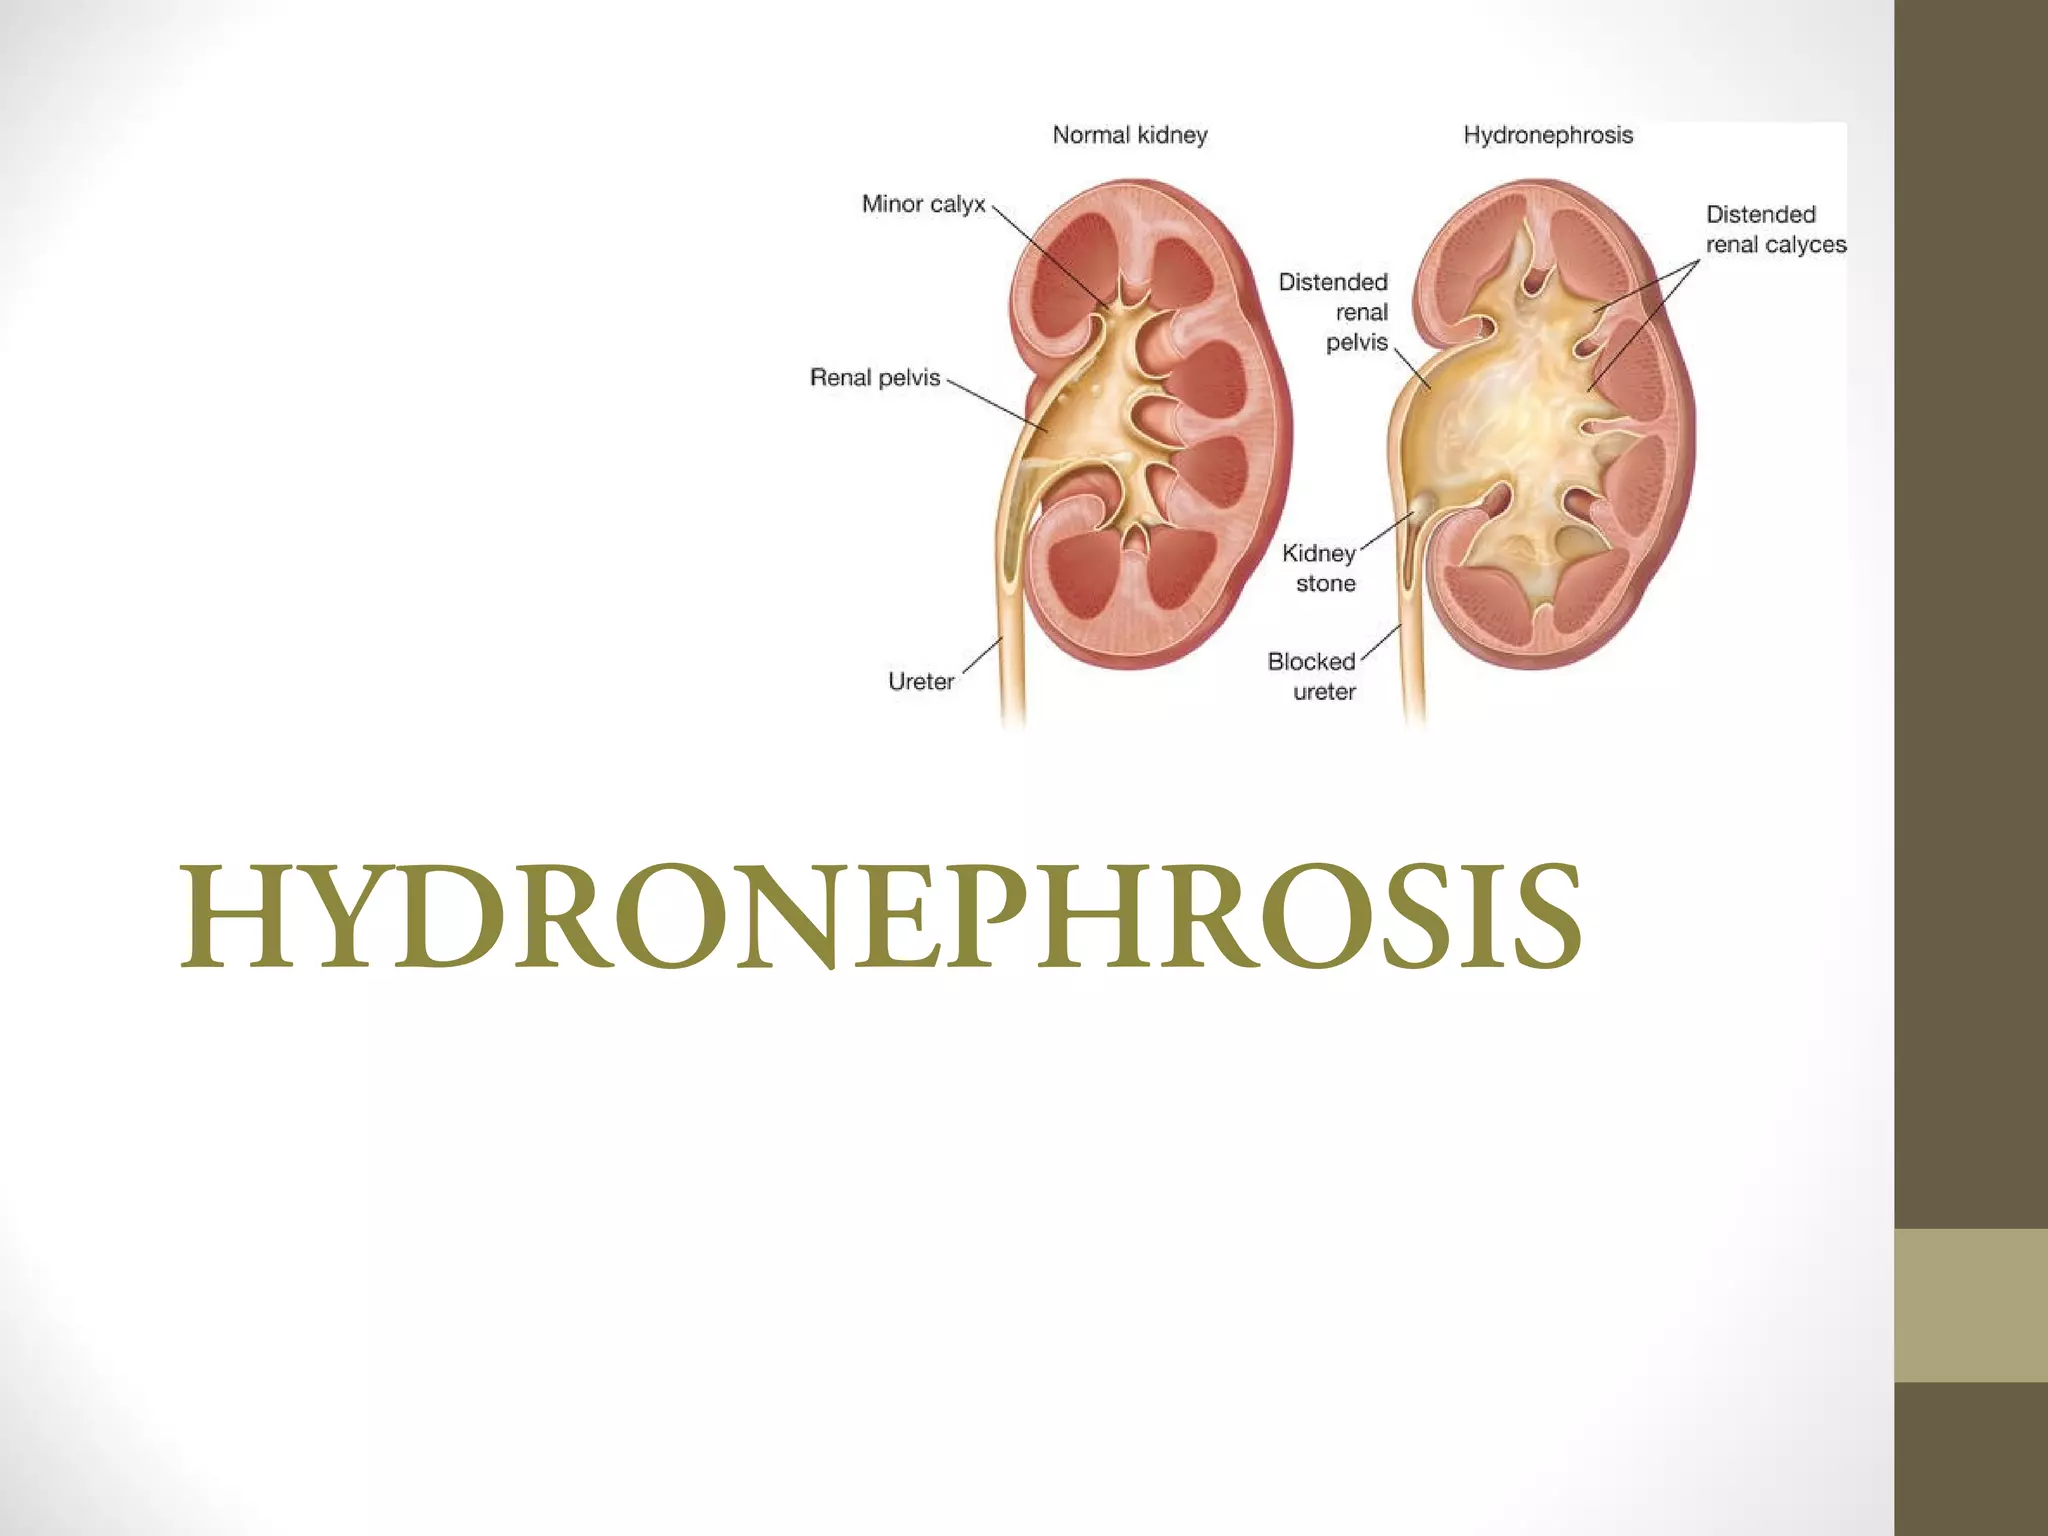

Hydronephrosis is the dilation of the renal pelvis and calyces caused by obstruction of urine flow from the kidney. It can be caused by issues in the ureter, bladder, or urethra that limit urine outflow. Unilateral hydronephrosis may cause dull flank pain while bilateral obstruction can lead to decreased urine output. Left untreated, hydronephrosis can damage kidney tissue and impair renal function. Diagnosis is made through imaging tests like intravenous pyelogram. Treatment focuses on resolving the underlying cause of obstruction.